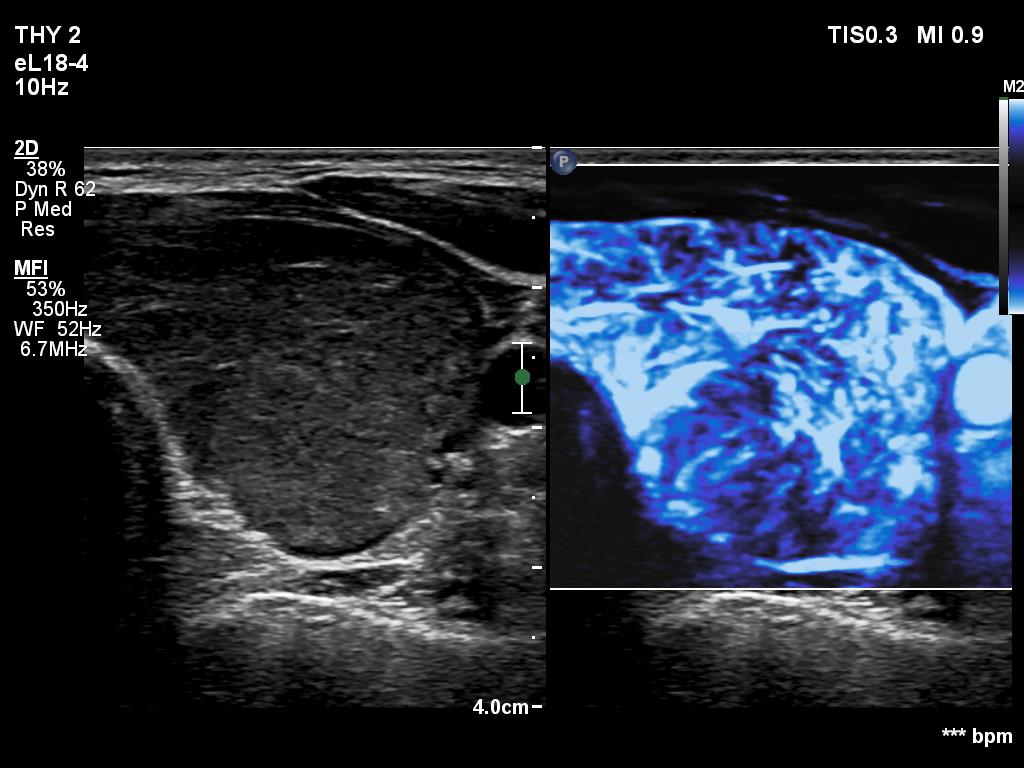

Right lobe, longitudinal scan

Left lobe, transverse scan, microflow imaging. The vascularity is very increased.